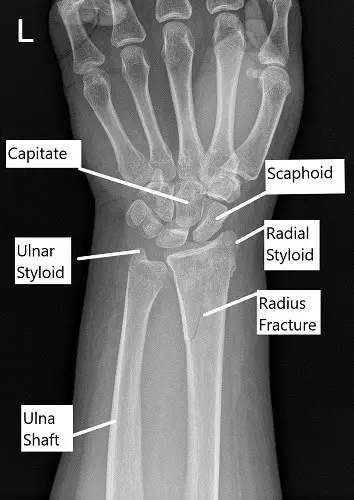

X-ray showing distal radius fracture in AP view.

The x-ray of the left wrist revealed an oblique fracture of the distal left radius which communicates with the articular surface. There is a nondisplaced fracture of the distal left ulna. Further radiological studies in the form of CT scan revealed rotation of the distal fragment, with approximately 24 degrees of resulting apex-volar angulation.